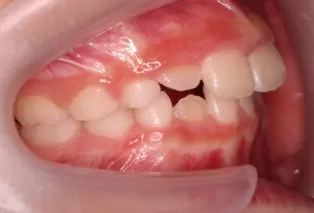

Intraoral photos